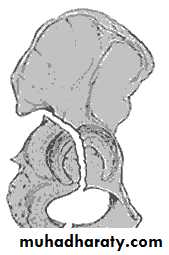

HIP DISLOCATION

anatomy

Injuries of the hip and femurThe magnitude of force needed to dislocate the hip joint particularly well-contained by virtue of its bony and soft-tissue anatomy.

is so great that the dislocation is often associated with fractures - either around the joint or elsewhere in the same limb.

Hip dislocations are classified according to

the direction

of the femoral head displacement:

Traumatic Dislocations of the hip.

Posterior.Anterior.

Central.